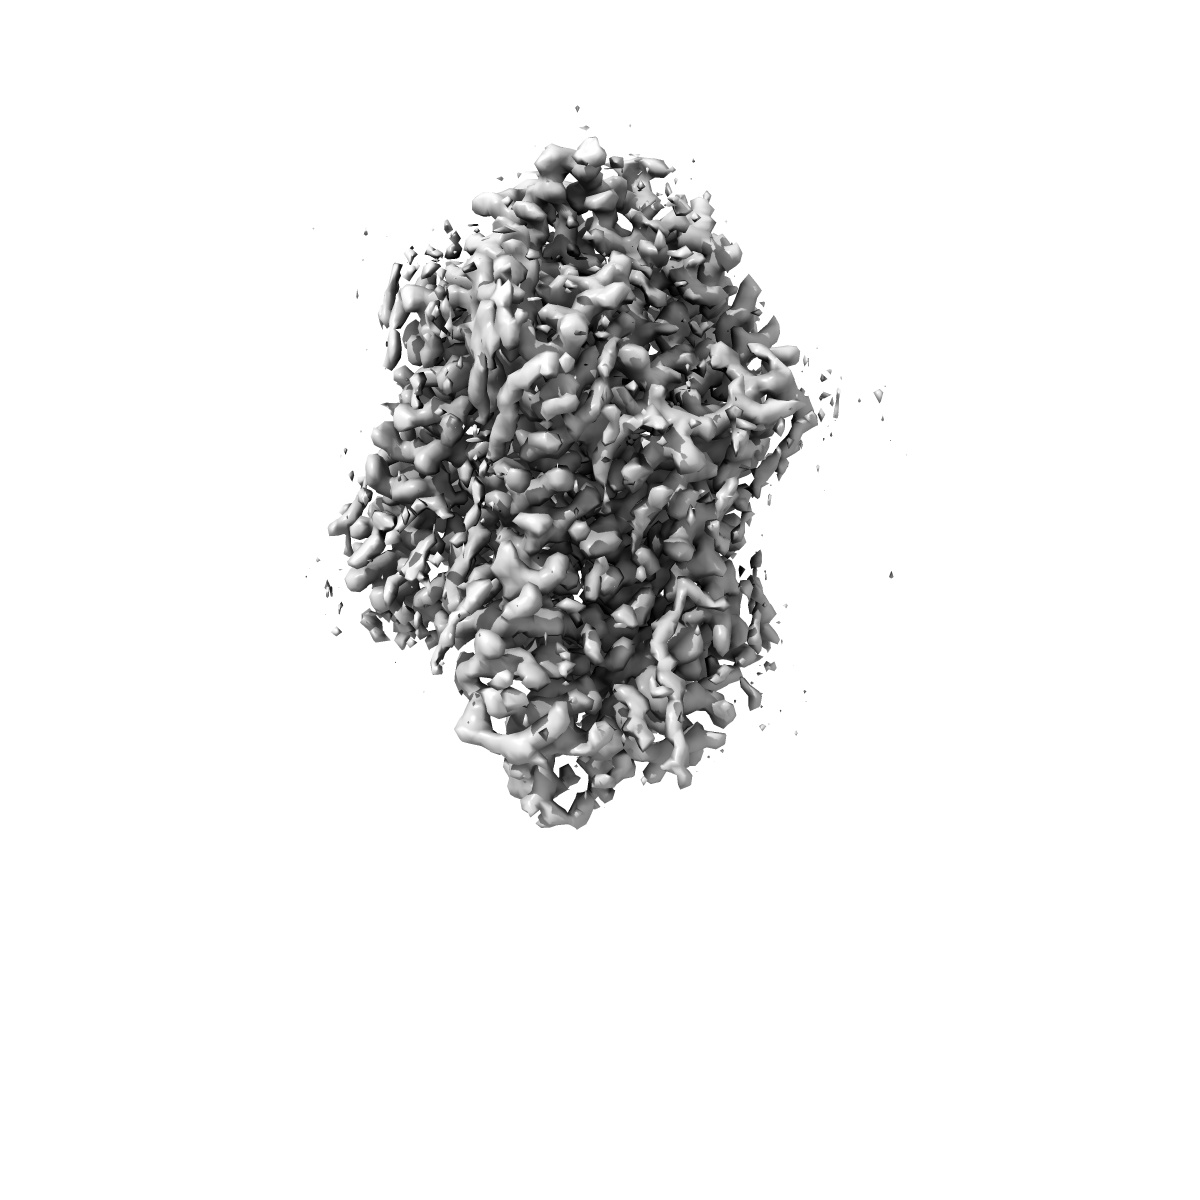

Cryo-EM structure of human norepinephrine transporter NET in the presence of the antidepressant desipramine in an inward-open state at resolution of 2.5 angstrom.

Single-particle2.5 Å

Molecular basis of human noradrenaline transporter reuptake and inhibition.

(2024) Nature , 632 , 921 - 929